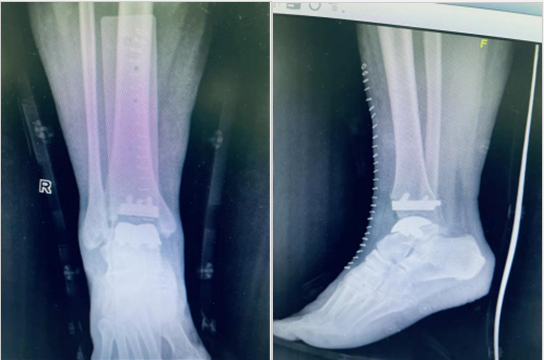

经过详细的术前分析,王文波教授、张涛副教授团队为李女士成功实施右侧全踝关节置换术,术中准确定位并置入踝关节假体,在成功松解软组织的同时又避免了血管神经结构的牵拉破坏,同时采用合适的假体,确保踝关节的稳定性,整个手术过程患者生命体征平稳。术后一周,患者康复出院。

术后复查X线提示右侧人工踝关节置换术后,假体未见松脱、移位及断裂